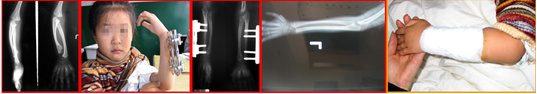

病例5:蔡某,女,28 岁。儿时右肱骨骨髓炎致右上臂停止生长,较对侧短缩11cm。

病例6:患儿,女,12岁,左尺骨骨软骨瘤,致左前臂畸形